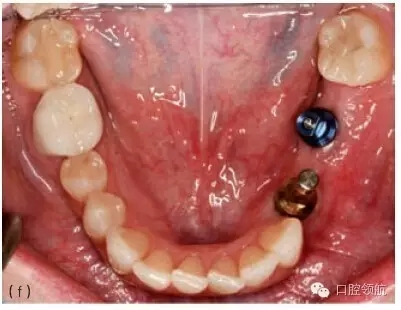

圖10.1 (a)個(gè)性化基臺(tái)連接在種植體上的牙合面觀。螺絲的長(zhǎng)軸對(duì)應(yīng)的是種植體的長(zhǎng)軸,螺絲的長(zhǎng)軸傾斜,基臺(tái)螺絲孔通頰側(cè)面。(b)成品基臺(tái)的頰面觀,螺絲的入口清晰可見。(c)上頜種植體的轉(zhuǎn)移替代體,反映種植體頰側(cè)傾斜的角度。(d)使用個(gè)性化鑄造基臺(tái)能獲得良好的美學(xué)效果。(e)轉(zhuǎn)移替代體顯示種植體的方向不平衡。(f)轉(zhuǎn)移替代體在口內(nèi)頜面觀,如圖可見遠(yuǎn)中種植體舌傾。(g)制作診斷蠟型以確定最終修復(fù)體的外形。(h)個(gè)性化基臺(tái)的代型,遠(yuǎn)中種植體的螺絲入口位于近中舌側(cè)位。固定局部義齒將會(huì)粘結(jié)于個(gè)性化基臺(tái)上。